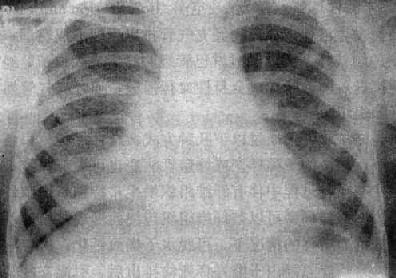

由于病灶系多次血行播散所形成,故X线表现为大小不一、密度不同、分布不均的多种性质的症灶(图3-1-23)。小者如粟粒,大者可为较大的结节状,主要分布于两肺上、中野,下野较少。早期播散的症灶可能已经钙化,而近期播散的病灶仍为增殖性或渗出性。本型结核发展较慢,经治疗新鲜病灶可以吸收,陈旧病灶多以纤维钙化而愈合。恶化时病灶可融合并形成空洞或逐渐转为慢性纤维空洞型肺结核。

图3-1-23 慢性血行播散型肺结核

两肺野布满大小不一、密度不同、分布不均的病灶,

下野较少,膈位置低而平